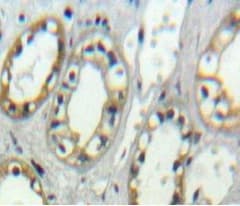

Rabbit Polyclonal CD11d antibody. Suitable for WB, IHC-P and reacts with Mouse, Human samples. Immunogen corresponding to Recombinant Fragment Protein within Mouse Itgad aa 850-1150.

Applications IHC-P, WB